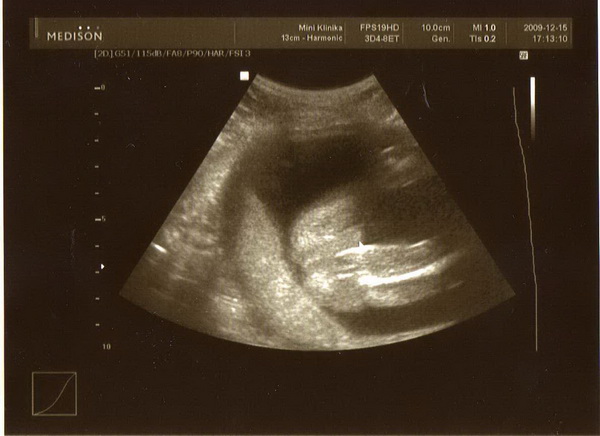

Épp csak egy gyors info :D

Most jövök UH-ról és minden nagyon rendben a kicsivel meg velem is, méretek megfelelőek, tehát nagy az öröm, már alig vártam megnyugodhassak :roll:

Na és erősödik a fiúcsapat, ugyanis 1oo % hogy kisfiú, össze sem tette a lábát :)) Tehát apánál maximális az öröm, én meg elkezdek más színekben gondolkozni és alig várom már h ölelhessem:D